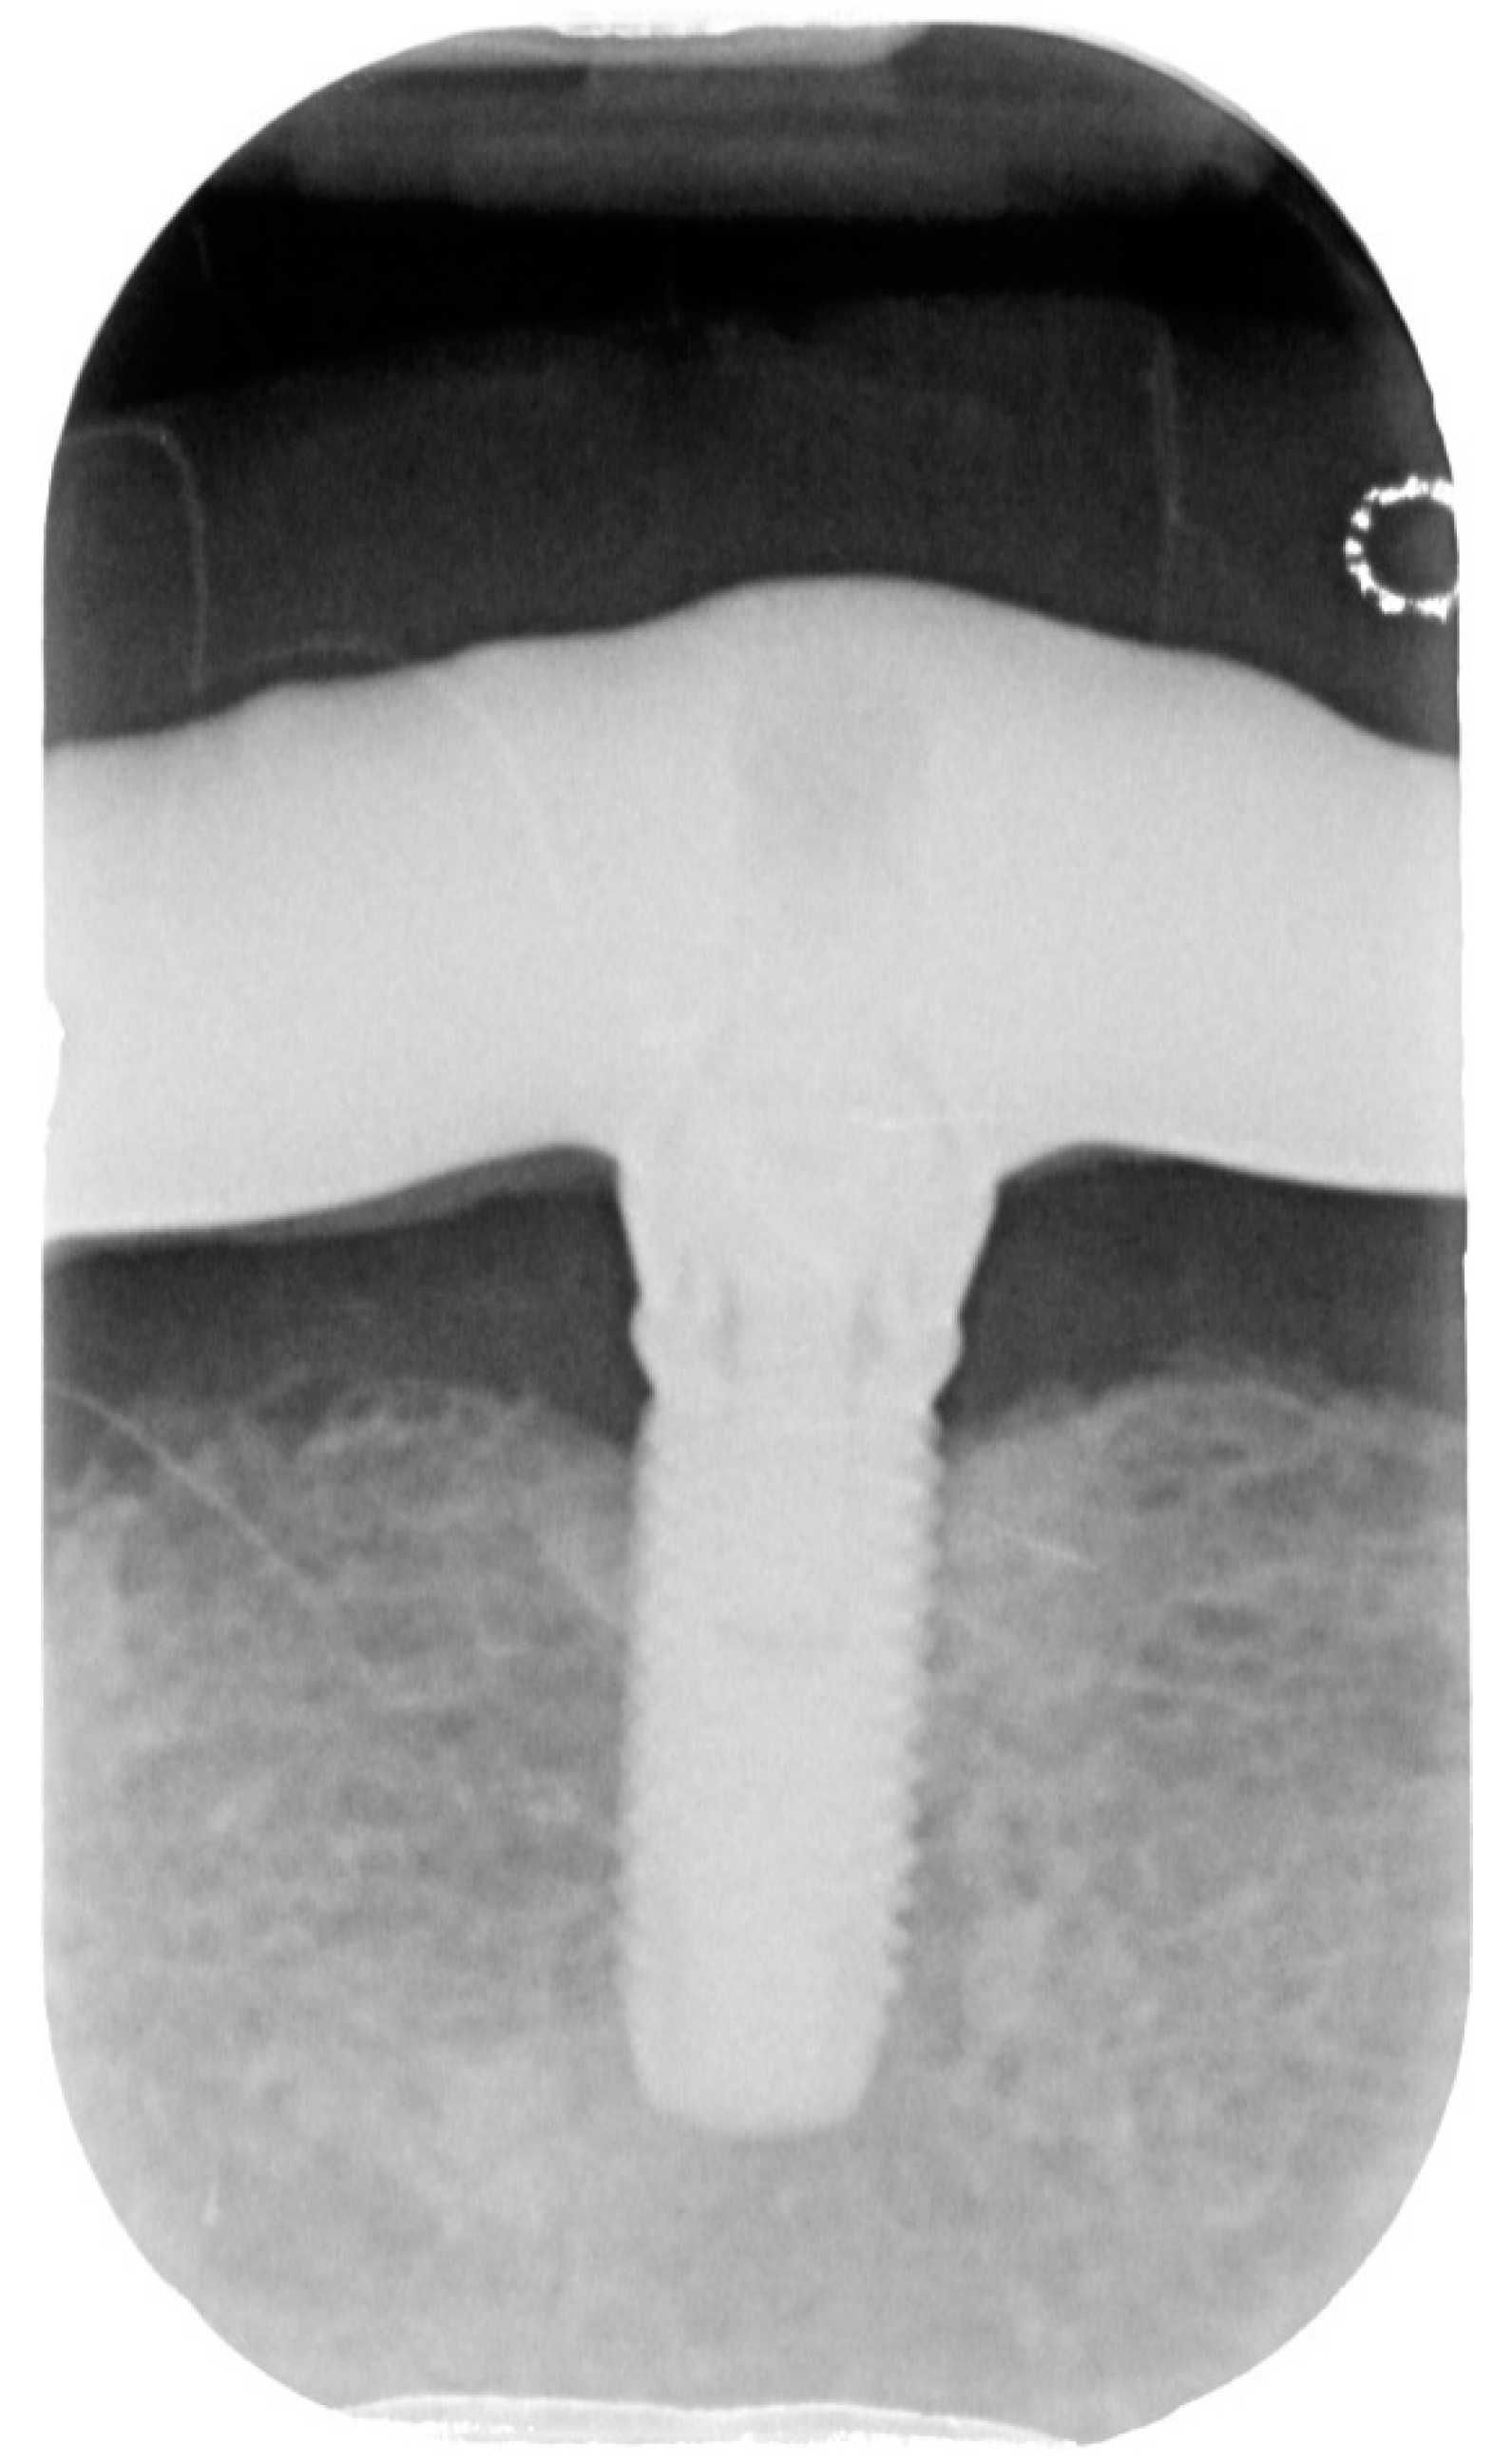

2.3. Case Report 3